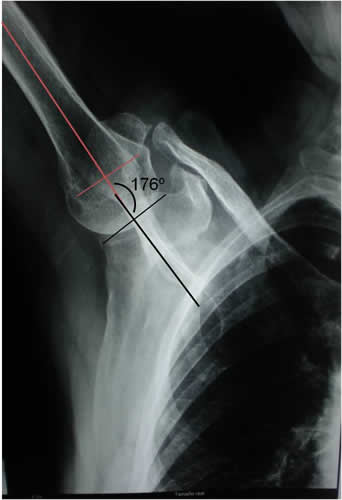

- Paciente: CP 76 años, femenino

- Motivo de consulta: Dolor e impotencia funcional en hombro derecho. Capsulitis adhesiva. Síndrome de Impacto.

- Inicio de tratamiento: Enero de 2010

- Fin del tto.: Marzo de 2010

- Total de sesiones realizadas: 8 sesiones